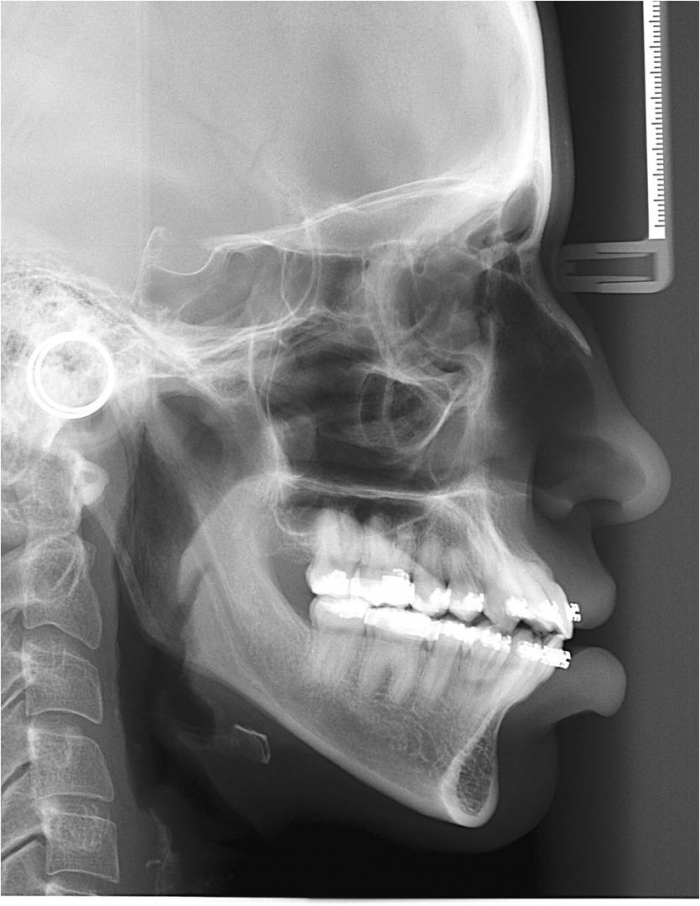

Telerradiografia inicial

Telerradiografia após a cirurgia